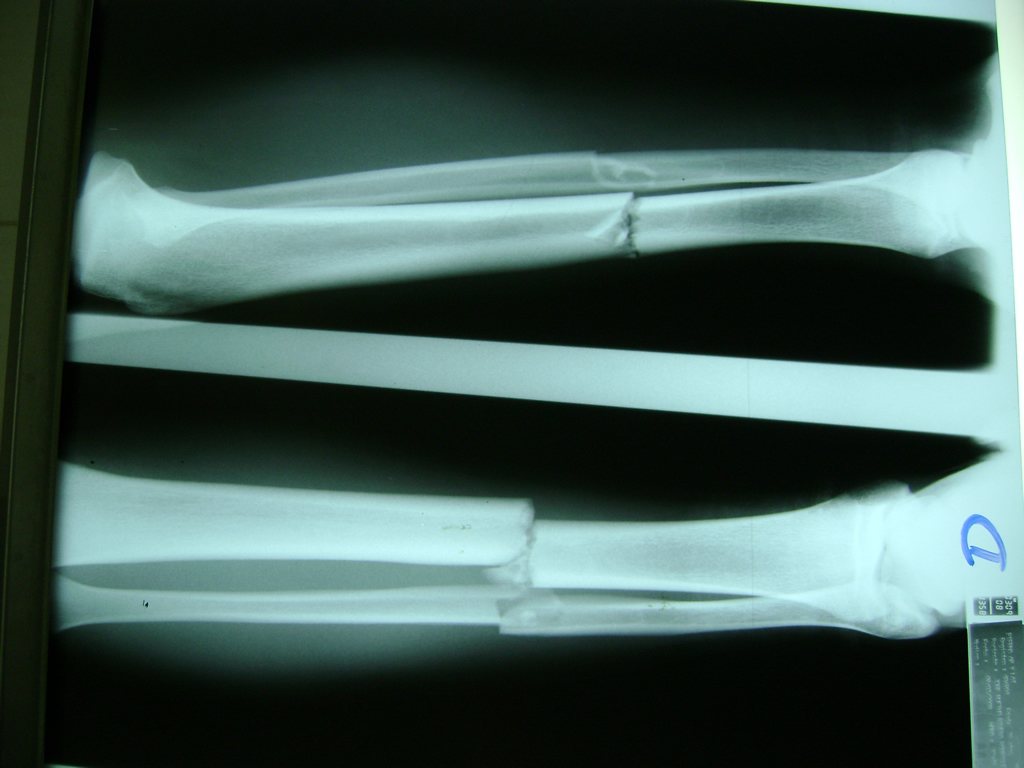

Cirugías de Húmero - Perone y Tibia

Aunque cada uno de estos huesos puede fracturarse por separado, normalmente la rotura es una lesión que se produce de forma conjunta

La mayor parte de las roturas implican a la parte proximal del hueso (parte del hueso próximo a la rodilla) o a la parte distal (parte del hueso cerca del tobillo).

Debido a la fina cobertura de piel que recubre la tibia y el peroné, las fracturas generalmente son abiertas, es decir, el hueso roto rasga la piel, atravesándola. Las fracturas de tibia y peroné generalmente se producen por un fuerte impacto o torsión.